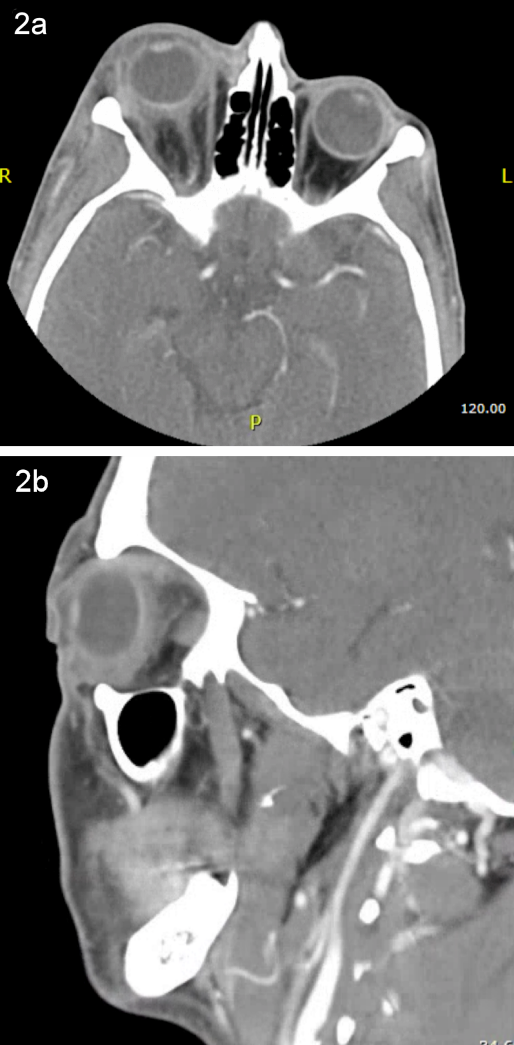

The white blood cell count was 12,800 cells/mm3, blood glucose was 331 mg/dl, and liver transaminases within normal limits. A computed tomography (CT) scan of the orbits showed right-sided orbital cellulitis with significant fat stranding centered around the globe and no significant sinus disease (Figure 2 [Fig. 2]). Ocular ultrasound demonstrated hyperechoic material in the vitreous cavity consistent with vitritis (Figure 3 [Fig. 3]). Abdominal ultrasound revealed mild hepatomegaly without a hepatic abscess.

Figure 2: Axial (a) and sagittal (b) computed tomography (CT) post-contrast images showing proptosis of the right eye with orbital fat stranding focused primarily around the globe. There is no evidence of sinus disease or subperiosteal abscess.